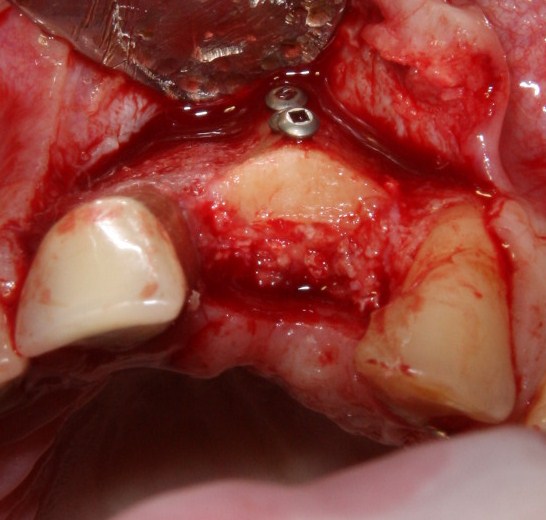

Делаем разрез, скелетируем костную ткань:

Как видите, коллагеновая мембрана полностью резорбировалась, а костный блок прижился и интегрировался на челюстной кости. Можно убрать винты:

и приступить к подготовке лунки под имплантат:

По существующим правилам, при установке импланта в области фронтальной группы зубов, его ось должна выходить на небную поверхность коронки или режущий край. Чего мы и добиваемся, контролируя процесс с помощью пинов.

Я планирую установить имплантат Dentsply Friadent XiVE диаметром 3.8 и длиной 13 мм. Это оптимальный размер импланта для протезирования боковых резцов.

Установка импланта:

Убираем имплантодержатель. Обратите внимание, что полированная фаска вокруг шейки импланта находится над уровнем костной ткани. Чрезмерное погружение импланта — весьма распространенная имплантологическая ошибка.